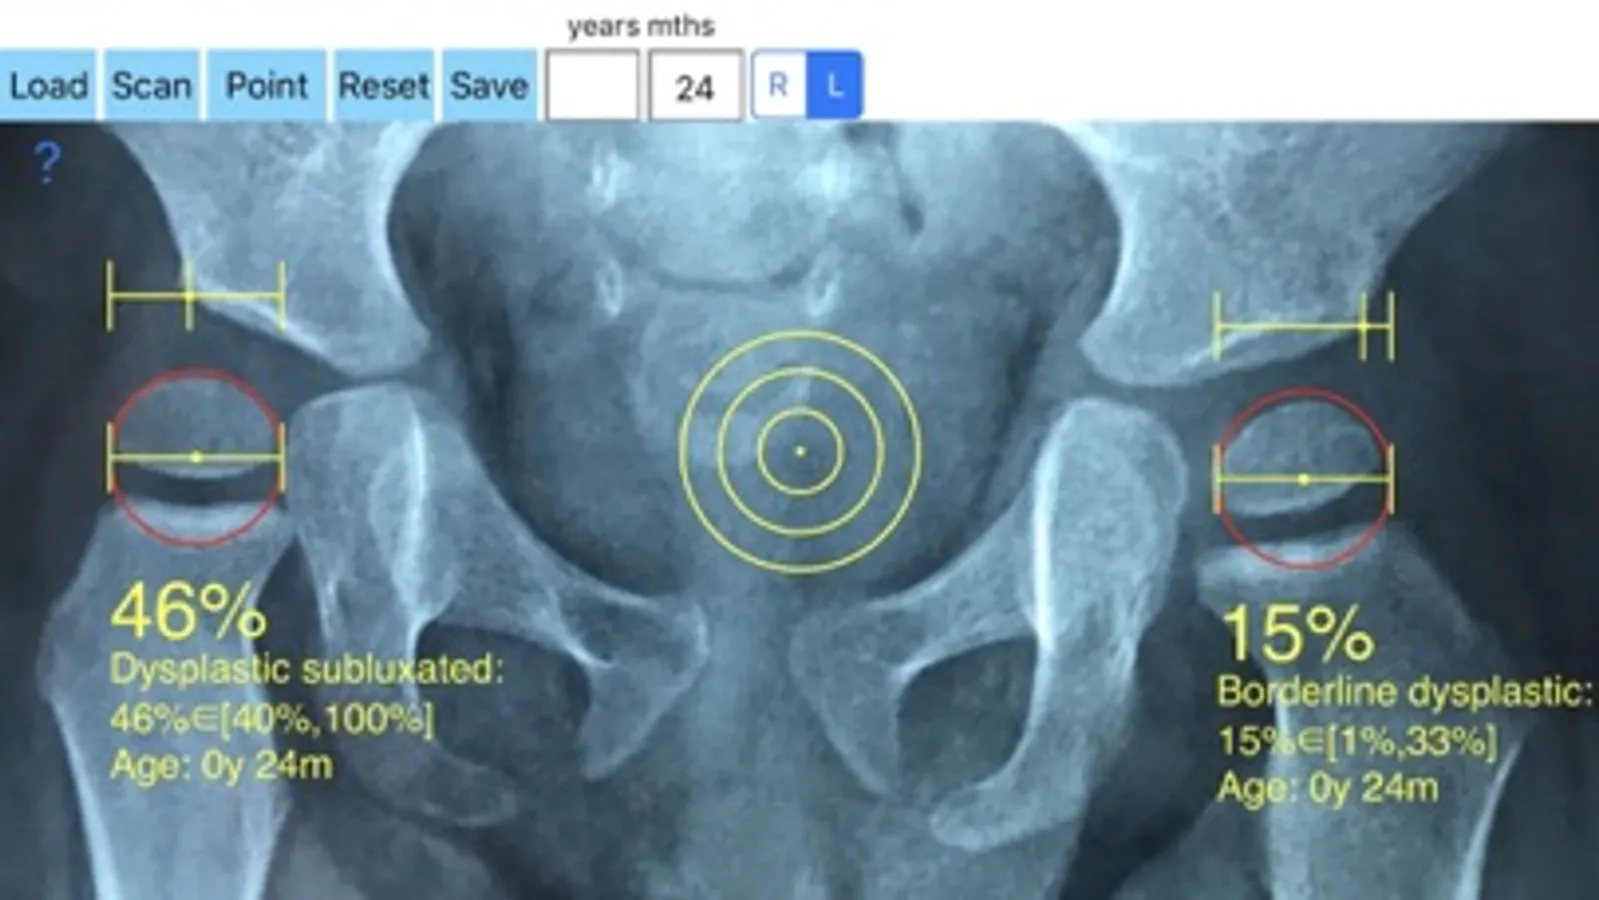

-Offers a very convenient way to determine the most accurate possibly way of measuring the percentage of femoral head which is not covered. By the aid of a circular transparent template which help to mark accurately the points of interest and the dynamic graphics who has been especially developed, by clicking only two points the percentage is calculated. By inputting the age of the patient in the App, the measured values in percentage are compared with values from normal reference database accordingly. In cases the percentage of uncovered femoral head of the hip is beyond the normal range for the relevant age, the hips are categorised as borderline dysplastic or dysplastic ready to subluxate or subluxated, dysplastic luxated or dislocated .